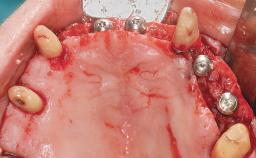

Conventional Loading of Eight Implants in the Maxilla and Final Restoration with a Full-Arch Gold-Ceramic FDP

# of Implants 8

Type of Implants One-Piece

Bone Augmentation Horizontal|Staged|Vertical

Augmentation Materials Autogenous block(s)

Defining Characteristics Fully edentulous upper jaw to be rehabilitated with four or more implants

Modality Fixed hybrid bridge on 5+ implants